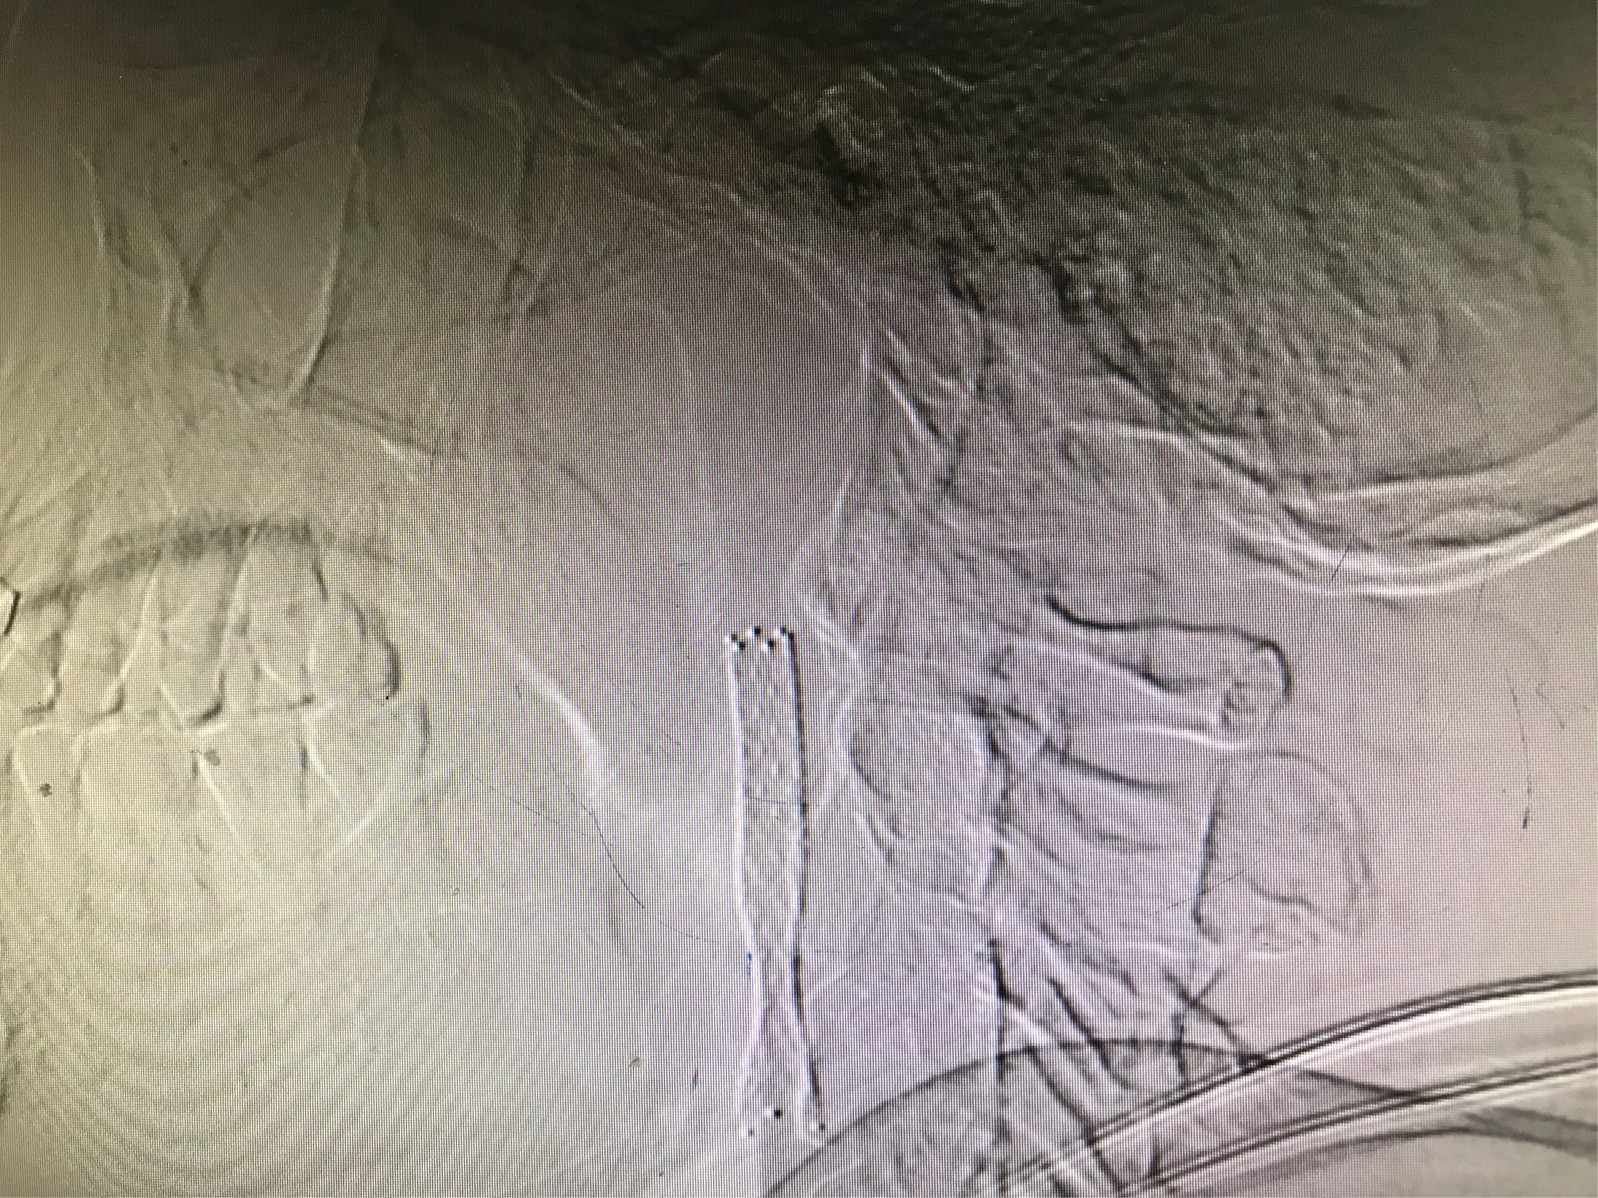

术中保护伞及球囊到位良好

保护伞全程保护,阻挡可能脱落斑块,安全第一

支架植入完成,效果良好